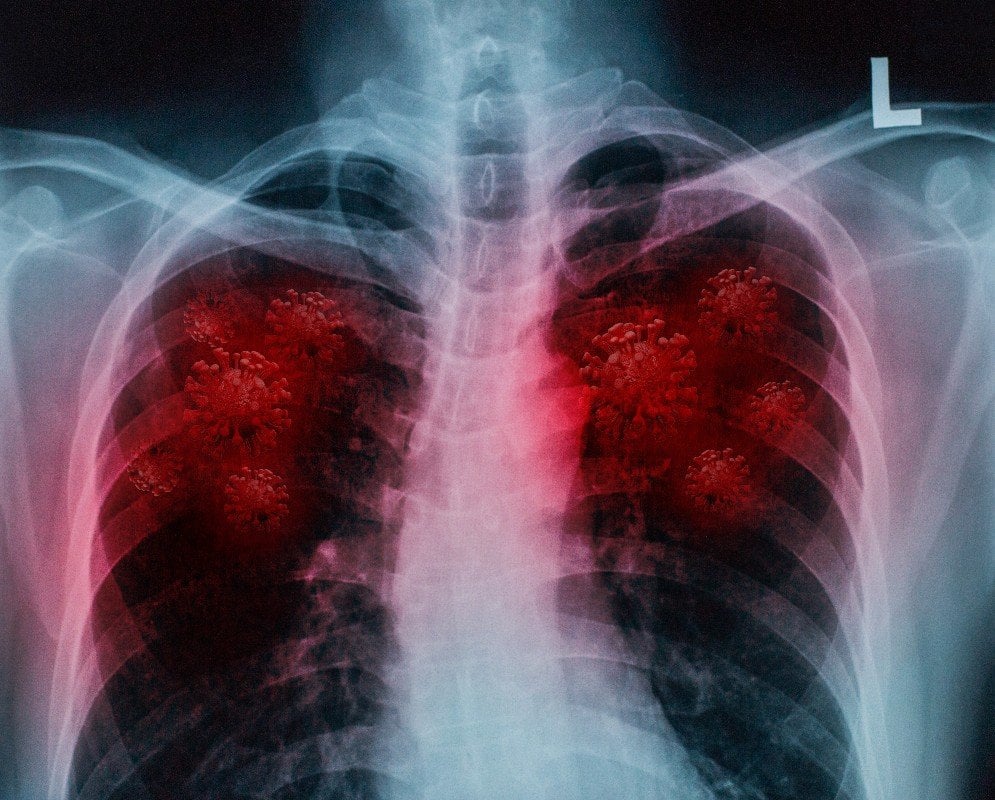

La Dr Brittany Bankhead-Kendall, une chirurgienne américaine tire la sonnette d’alarme. Les poumons des personnes guéries de la COVID-19 sont dans un moins bon état que ceux des fumeurs. La professionnelle qui a traité des centaines de malades a appuyé ses propos publiés sur Twitter avec des photos de scanner.

La chirurgienne et professeure assistante au TexasTech University Health Sciences Center prévient qu’il est rare que les radiographies des patients atteints de la COVID-19 reviennent sans cicatrice et lésion visible. Elle a écrit via son compte Twitter, le 4 janvier 2021 : "Je ne sais pas qui a besoin d’entendre cela, mais les poumons post-Covid semblent pires que n’importe quel poumon des plus gros fumeurs que nous ayons jamais vu". Elle ajoute ensuite "ils s'effondrent. Ils ont des caillots. Et l'essoufflement persiste ... encore et encore ... et ainsi de suite".

Interrogée après la parution de son message par la rédaction de la chaine CBS à Dallas/Forth Worth, la professionnelle de la santé a appuyé ses propos avec 3 scanners : des poumons sains, ceux d'un fumeur et ceux d’un patient ayant eu la COVID-19.

La Dr Bankhead-Kendall ne cache pas son inquiètude dans les médias. Selon son expérience avec la maladie, tous les patients symptomatiques présentent une radiographie pulmonaire problématique. Mais ils ne sont pas les seuls ! 70 à 80% des patients ayant eu des formes asymptomatiques ou très légères présentent des lésions importantes et nombreuses.

En effet, les scanners des poumons sains sont majoritairement noirs, ces zones sombres montrent l'air présent. Avec le poumon du fumeur, des lignes blanches indiquent des cicatrices et une congestion. Alors que le scanner des poumons COVID est rempli de taches blanches.

La chirurgienne prévient : "si vous ne ressentez pas de problèmes maintenant, le fait que cela soit sur votre radiographie thoracique indique certainement que vous pourriez avoir des problèmes plus tard”.

Elle reconnaît néanmoins qu’il est encore tôt pour connaître l’étendue de l’impact du coronavirus sur le corps ou pour savoir si les nombreuses lésions détectées dans les poumons post-covid peuvent finir par guérir. La médecin conseille en revanche aux personnes ayant été infectées par le SARS-CoV-2 de consulter leur médecin si des troubles persistent après la guérison, et plus particulièrement en cas d'essoufflement.